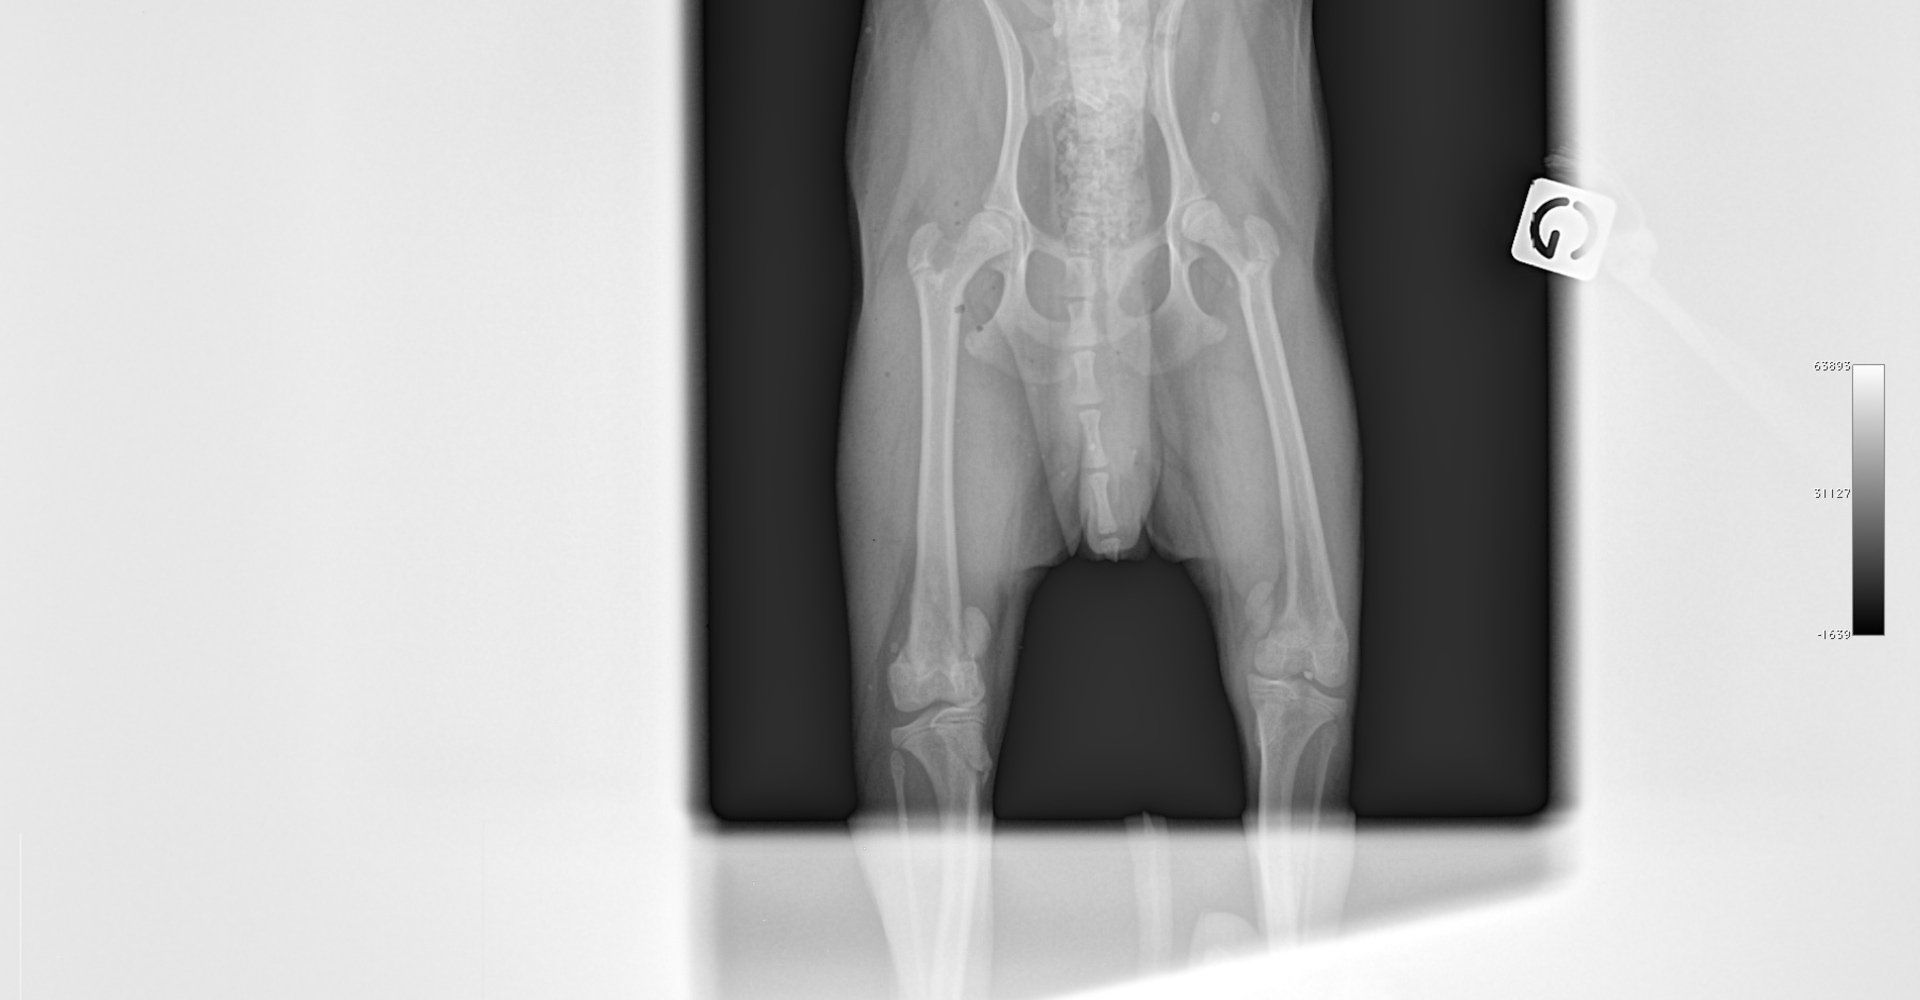

Fracture Salter-Harris sur un chaton Européen de 10 mois

Spike, chaton européen mâle de 10 mois, a été présenté en consultation pour boiterie du membre postérieur droit à la suite d'une chute depuis le 1er étage.

A la radiographie, une fracture de type Salter-harris 1 est diagnostiquée, avec déplacement de l'about discal.

Une réduction de la fracture par pose de 2 broches en croix a été réalisée.